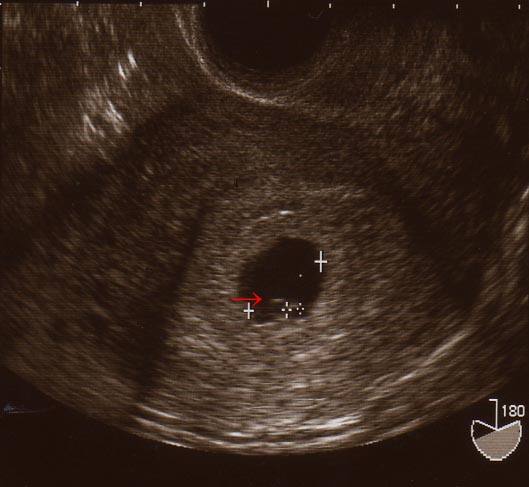

2mmの赤ちゃんが、ビシッと子宮にいました!!!

その小さな、小さな新しい命には、ちゃーんと心拍まであるんです!